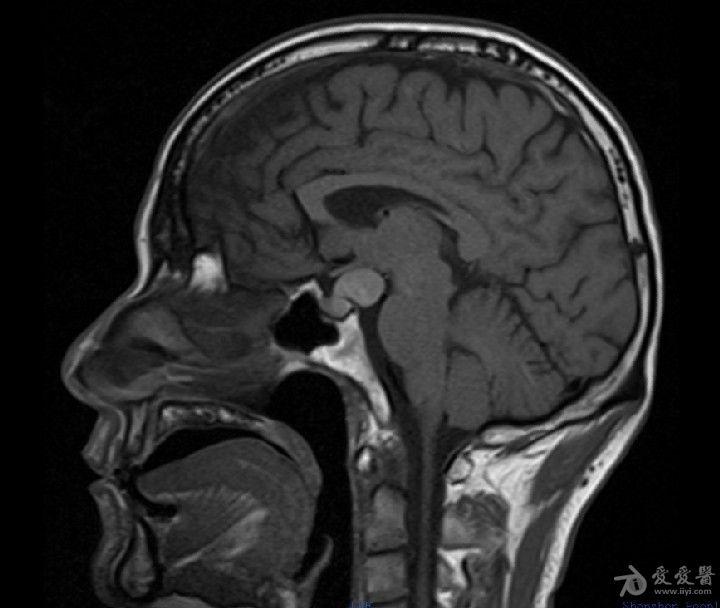

t1wi 高信号的神经垂体前方case 5:m/52y矢状位 t2wi 示:高信号囊肿和